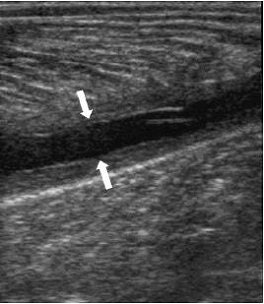

![]() |

| Same patient as above. The longitudinal image four weeks later shows the reparative process as a hypoechoic area (arrows) and a well-defined anechoic fluid collection. Kwak H, Han Y, Lee S, Kim K, Chung G, "Diagnosis and Follow-up US Evaluation of Ruptures of Medial Head of the Gastrocnemius ('Tennis Leg')," Korean J Radiol 7(3), September 2006. |